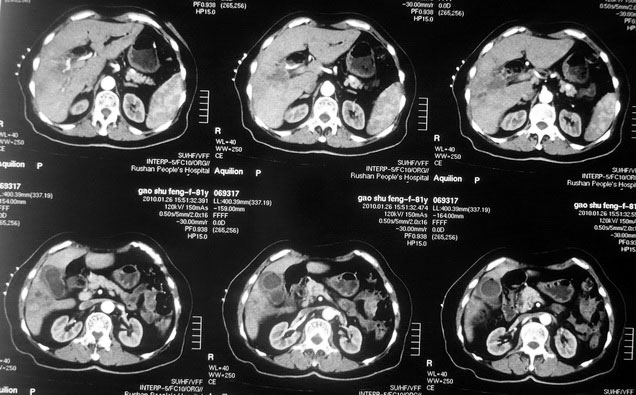

女,80岁既往有胆系手术史。近2月出现食欲不振,近20天出现畏寒发热,体重约下降10kg,体温一般在38℃左右。血常规wbc正常,中性比例88%,cea 10.3,afp、ca199均正常。做过一次肝穿,抽出约3ml仿佛脓性液体。这是她的增强ct扫描,请大家帮帮忙。另外想问问肝脓肿和胆管细胞癌的ct表现有什么区别。谢谢了。

【湘江一滴】化脓性胆囊炎及胆管炎,肝内胆管积气、积液、扩张;胆囊壁增厚、强化;胆周积液。未见肝内占位征象。

【shuiyuan】化脓性胆囊炎及胆管炎,肝内胆管积气、积液、扩张;胆囊壁增厚、强化;胆周积液.

肝脓肿动脉期呈明显环形强化或蜂窝状强化,胆管细胞癌动脉期强化不明显,且伴肝内胆管扩张。

【zenxisengming 】肝内胆管扩张积气,胆囊比环形增厚,胆囊周围渗出,未见占位性病变,应该是胆道化脓性感染

【sunbin】肝内见多个气体密度影伴气液面,胆囊壁增厚,胆囊周围低密度环绕,未见强化,支持化脓性胆管炎、胆囊炎。

最近复查ct,做了第二次穿刺抽脓,顺便做了涂片病理活检,结果找到恶性肿瘤细胞,诊断肝癌合并肝脓肿。看来大家都走眼了啊。